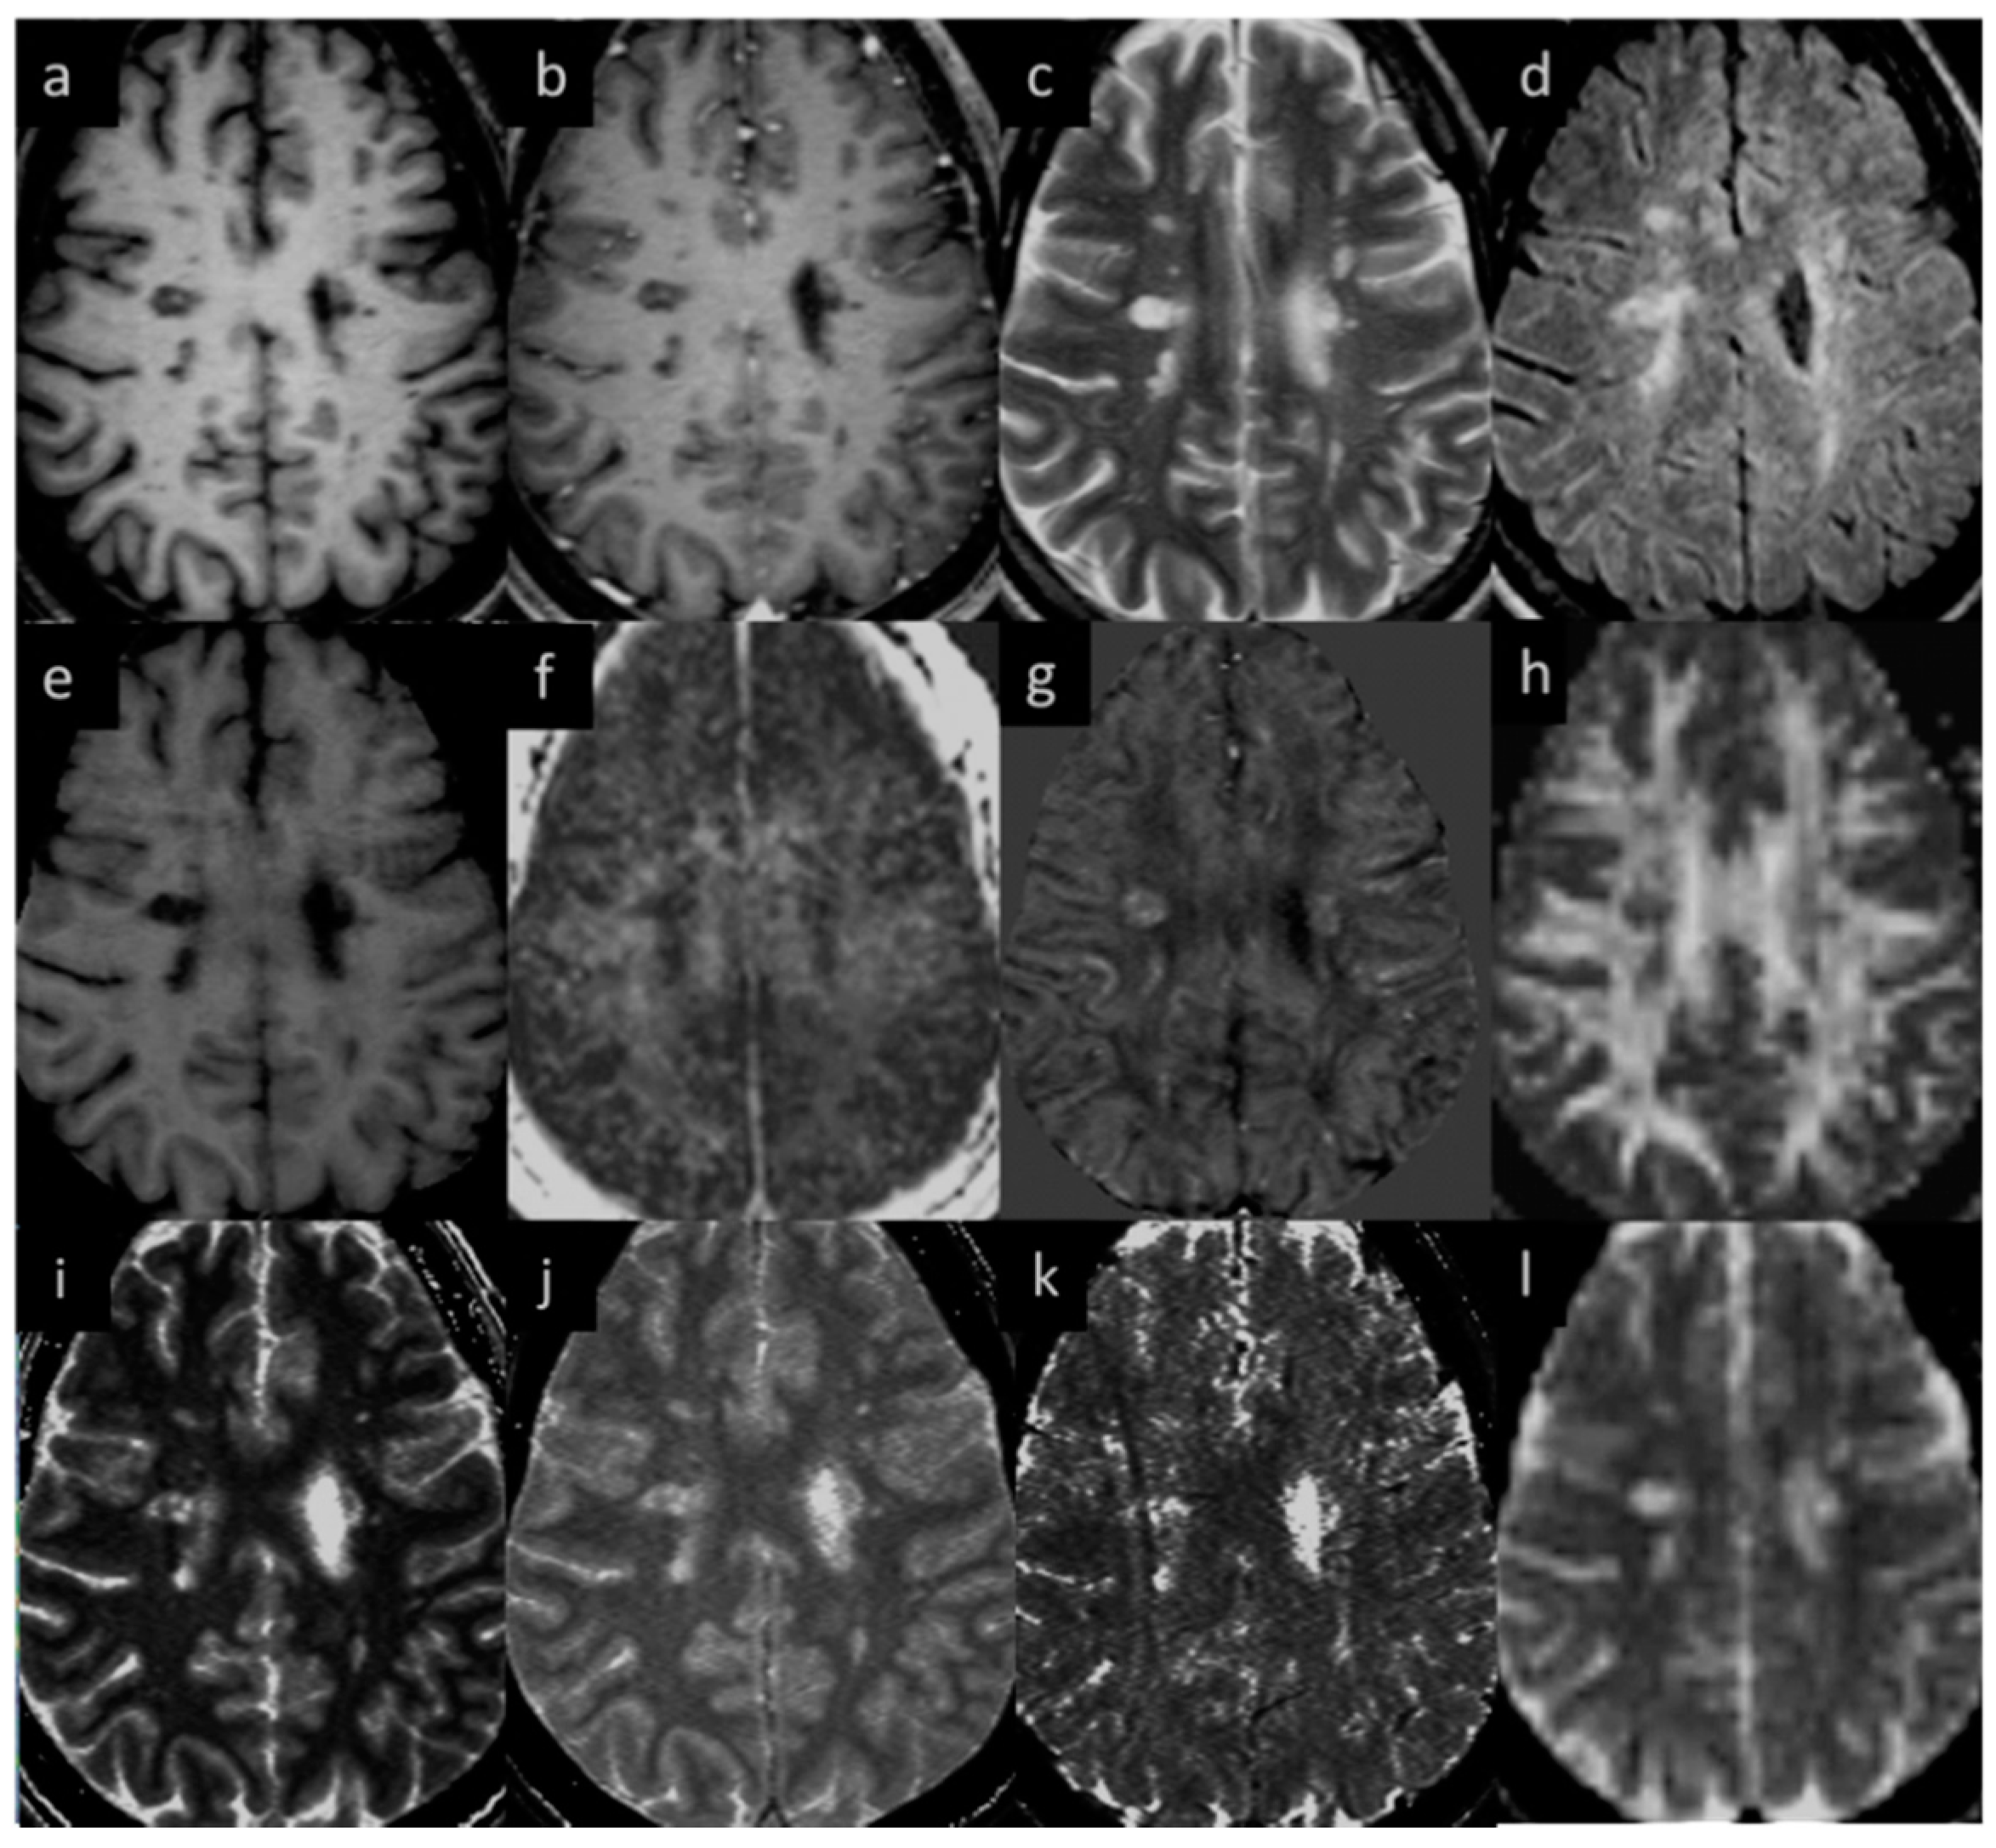

3.1. Lesions in MS Subjects

3.3. QSM ± Lesions

3.5. Correlation between Different Imaging Sequences